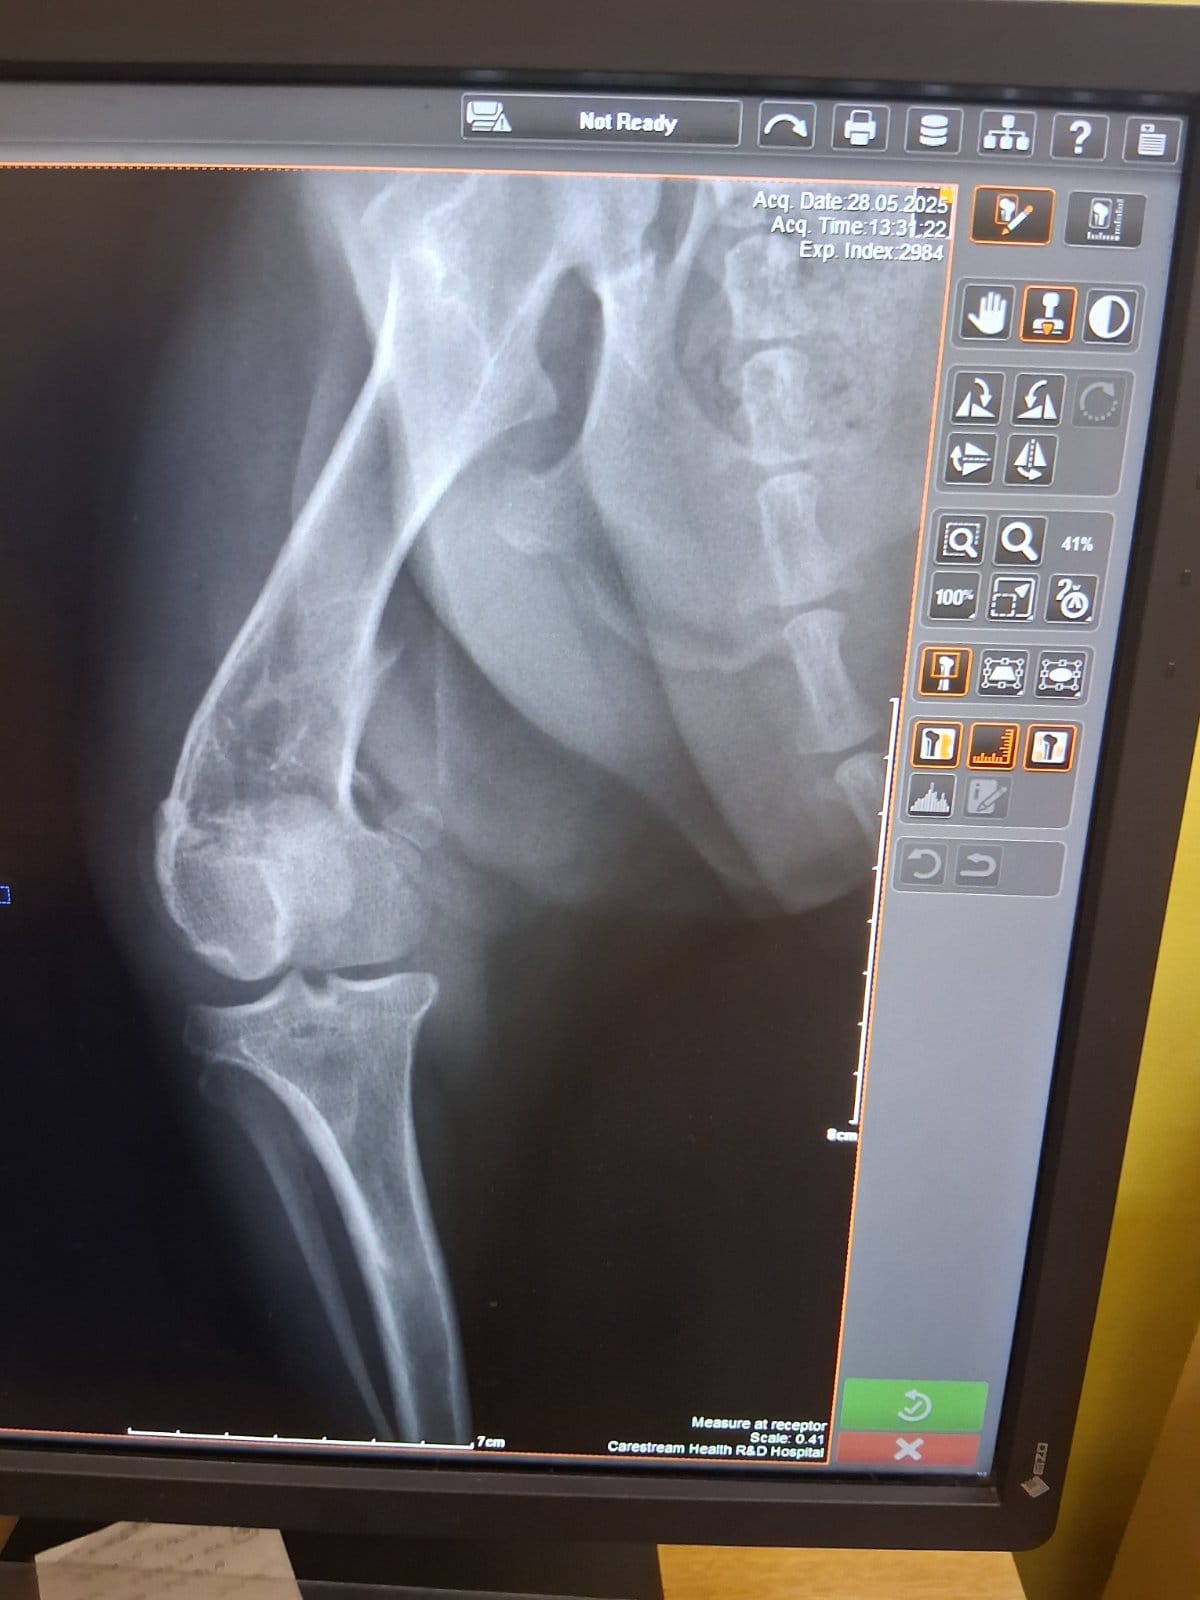

Im September 2025 haben wir Ihnen die kleine Finija vorgestellt: Gerade einmal vier Monate alt, wurde sie in einem erschütternden Zustand gefunden. Beide Hinterbeine waren gebrochen, eine Fortbewegung war für sie nur noch auf den Vorderpfoten möglich. Trotz starker Schmerzen zeigte Finija eine unglaubliche Willenskraft – ein kurzes Video aus…